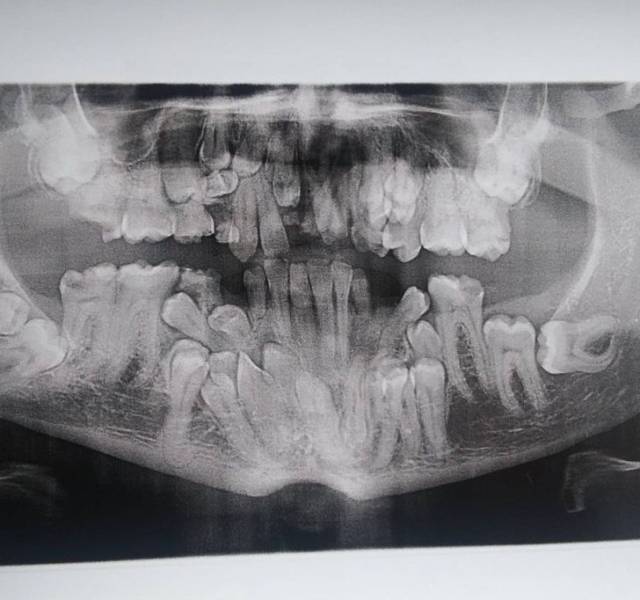

“I have a rare disorder called cleidocranial dysostosis. Got my first dental X-ray today and I have a lot of extra teeth.”